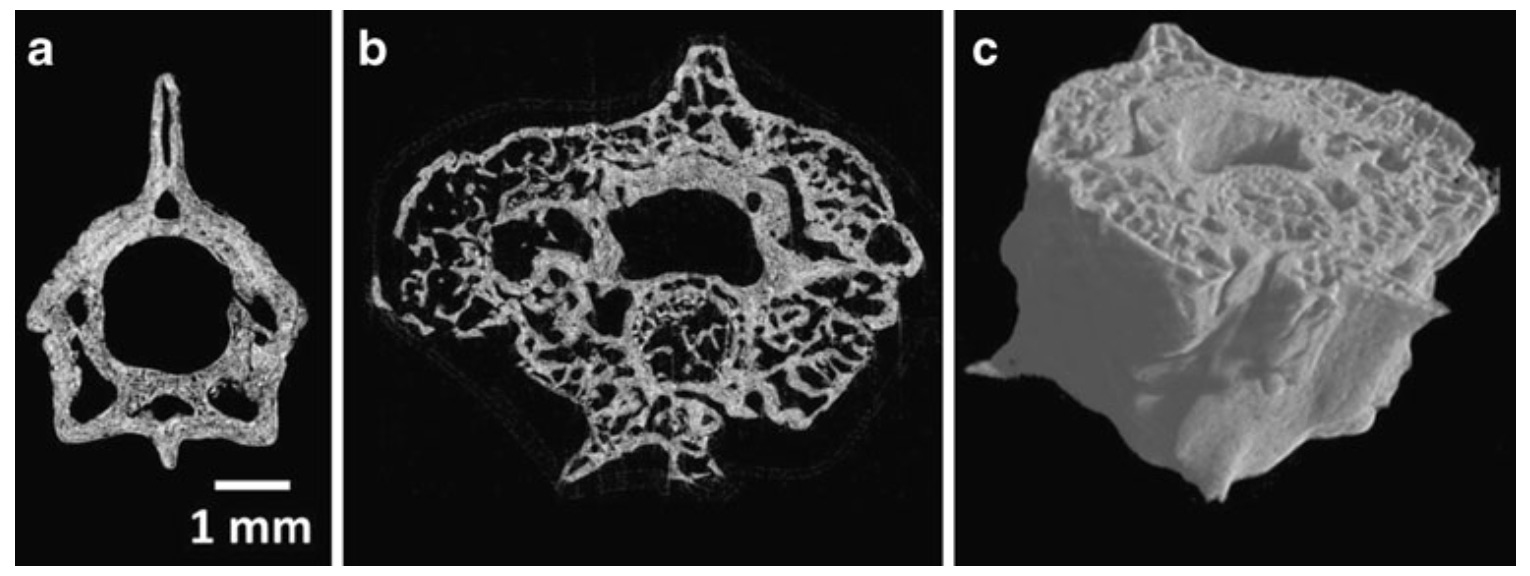

The left picture shows the micro-CT of the root section of the sunflower, and the right picture shows the distribution of the lead metal in the sunflower root (from J. Kaiser et al., 2007).

In 2010, the laser spectroscopy laboratory represented by Kaiser used LIBS technology combined with μCT technology to study and analyze the distribution of spine bone elements including Ca, Al, P, Na, etc. of snake deformity osteitis, and published "Investigation of The osteitisdeformans phases in snake vertebrae by double-pulse laser-induced breakdown spectroscopy" (Anal. Bioanal. Chem. 398:1095-1107, 2010)

The picture above shows the snake spine μCT, the picture below shows the snake's normal vertebrae (a) and pathological vertebrae (b) two-dimensional distribution of calcium and phosphorus.